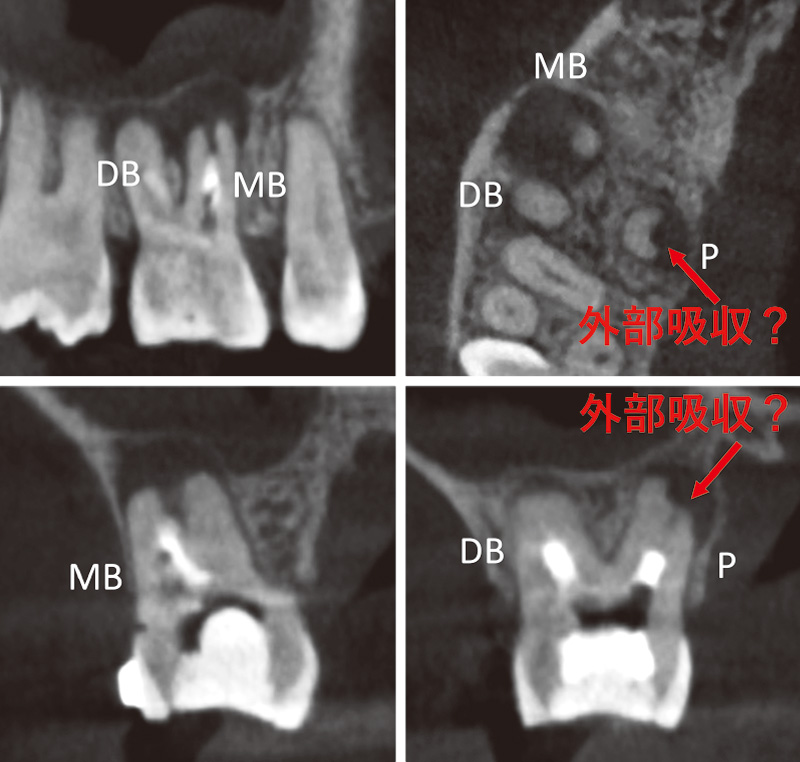

37歳男性。₇の咬合痛を主訴に来院した。デンタルX線画像(症例2-1)では根尖から遠心歯頸部に骨欠損がみられ、咬合接触時に動揺を示した。遠心歯周ポケットは6mmであったが、遠心の歯冠豊隆が大きいため、ポケット底部までポケットプローブが挿入できていない可能性を否定できず、ポケット底部の位置を推測することは困難であった。コーンビームCT(症例2-2A)では骨欠損が明確で、歯内-歯周病変の様相であった。また、MB根とP根は癒合しており(症例2-2B)、根管も途中で癒合していた(症例2-2C)。歯内-歯周病変と咬合性外傷の併発が疑われたので、歯冠補綴物を除去して感染根管治療を開始した。

3根管とも根尖には穿通できず、「ルートZX3」による高周波通電を行った。根管内に次亜塩素酸ナトリウム溶液を3mm程度注入し( 症例2-3A)、#10Kファイルを挿入可能なところまで入れ、メモリM4で通電した。1秒以内に根管内溶液は突沸し(症例2-3B)、さらに大きな気泡が発生した(症例2-3C)。このことから、ファイルが穿通できないのはレッジが原因で、根管は根尖病変に交通していると考えられた。さらに4回の通電を行ったが、途中で薬液の交換を行って歯根の過熱を防止した。

また、次亜塩素酸ナトリウムは100℃になると著しく分解が進み、高周波通電時の根管壁有機質の除去効果も低下するので、通電して突沸を2~3回繰り返したら、根管内の次亜塩素酸ナトリウム溶液を入れ替えている。DB根にも同様の通電を行い、水酸化カルシウム製剤を貼薬し、仮封して根尖部骨欠損の改善を4か月待った。